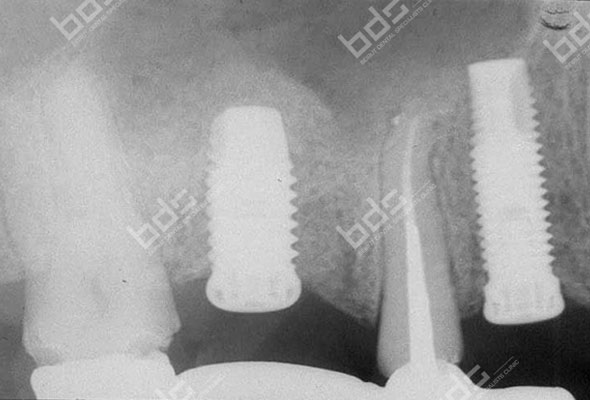

Dental Implants

Dental implants is a highly predictable procedure for the replacement of missing teeth, restoring in a very effective way both function and aesthetics. Dentures ,when loose, can cause severe personal and social handicaps that can be overcome by using implant supported fixed restorations. Implants can also serve to replace one or several teeth and save healthy adjacent teeth from being used as support for fixed bridges. The procedure can be very simple or more complex depending on the severity of the case. Implants used nowadays are mostly made of medical grade titanium. They are placed in the jaw and connected to abutments to serve as support for crowns or bridges.

Implant supported crowns are so natural looking ! Cad Cam technologies and innovative restorative materials give to the crown a perfect esthetic result. You will forget that you ever lost a tooth. your confidence is regained and your self image is completely restored. you do not need to hide your smile anymore nor feel embarrassed because of ill-fitting dentures. you may have had difficulty chewing. You will regain your full function! Implant-supported crowns will look and feel just like your own!

Your treatment needs to be properly planed and the implants and crowns placed under the best conditions to ensure long term success. With diligent maintenance, implants can last a lifetime. Long-term studies show very high success rates.

Because a dental implant will replace your tooth root, the bone is preserved. With a bridge, some of the bone that previously surrounded the tooth resorbs in time , part of a natural remodeling process Dental implants integrate with your jawbone, helping to keep the bone healthy and intact.

A single implant can be more esthetic and easier to keep clean than a bridge. Also, after several years of function, gums can recede around a bridge causing unesthetic exposure of the bridge margins. Resorbed bone beneath the bridge can be the cause of an unattractive smile. Also, the cement holding the bridge in place can wash out, allowing bacteria to proliferate unreached by the tooth brush resulting in decay of the anchoring teeth and bridge loss

Immediate Loading

Immediate loading refers to attaching a crown or a bridge to a newly inserted implant(s) at the time of implant placement. Simply put, the various procedures that were traditionally spread out over 4-6 months are carried out simultaneously. This means that you will always have fixed teeth during the treatment. Sometimes it is even possible to insert the final bridge at the time of implant placement.

Immediate loading is not always possible but may be indicated when selected factors are present: bone quality and quantity, primary stability when placed in bone, implants number and location and loading conditions .Having vast experience placing and immediately restoring implants will further enhance outcome. Our periodontists at the Beirut Dental Specialists clinic use the immediate loading technique with excellent success rates and consistantly great clinical results

The All-on-4 treatment concept was developed to provide edentulous patients with a functionally effective restoration using only four implants for an immediately loaded full-arch prosthesis. The four implants support a fixed prosthesis with 12 to 14 teeth and it is placed immediately on the day of surgery.